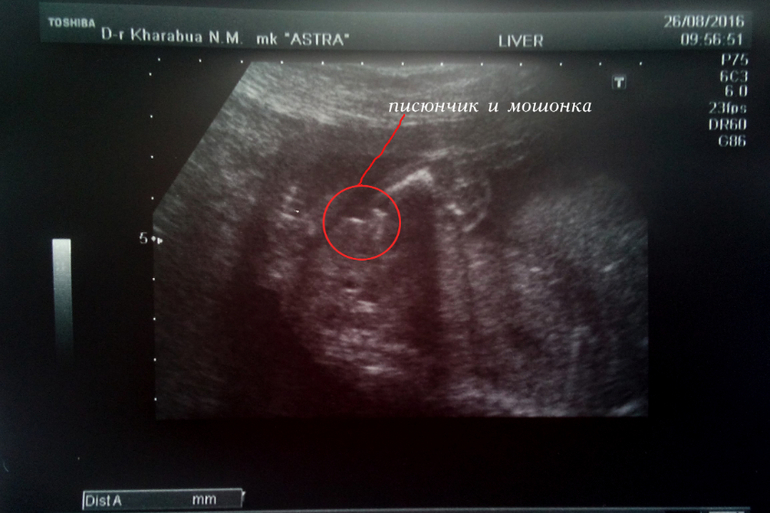

Ну и хотелось бы показать наше "достоинство" на фото. Я лично не сильно рассмотрела, но врач убедила, что девочки там быть даже не может. И писюн видно и мошонку, а так были бы явные "пирожочные" половые губы.